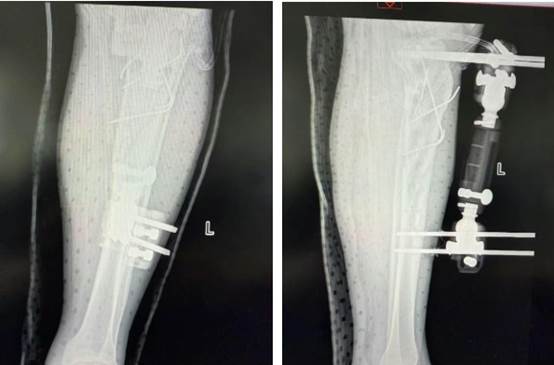

患者到院后,创伤外科值班医生王园迅速接诊,检查发现患者左下肢严重畸形、骨折断端外露,足背动脉搏动消失、皮肤苍白冰冷——提示下肢大血管损伤、肢体濒临坏死!时间就是生命!影像中心同步启动紧急检查绿色通道,CTA(CT 血管成像)结果迅速明确:腘动脉下段、左胫前动脉、胫后动脉及腓动脉上段未显影,确诊为「左胫腓骨开放性粉碎性骨折合并下肢主要血管断裂」。

在显微镜下,手术团队展开了高难度精细操作,实施「骨折外固定支架固定 + 胫前动脉吻合术 + 胫后动脉血栓取出及吻合术」。历经 5 小时鏖战,成功修复断裂的胫前动脉,清除胫后动脉血栓并精准吻合,终于成功重建下肢生命通道!目前患者生命体征平稳,受损肢体血运恢复良好。